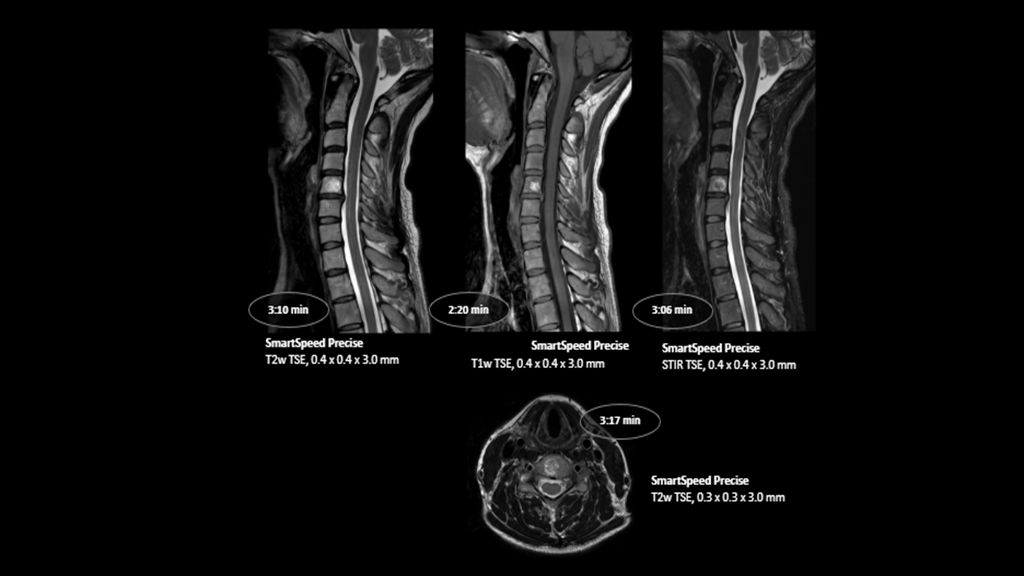

1. Compared to SENSE imaging, with no loss in image quality.

2. Reconstruction technology Compared to conventional (SENSE/ Compressed SENSE, SmartSpeed AI) imaging. Sharpness was evaluated with phantom scanning.

3. dStream based systems, not available for Prodiva and Multiva systems.